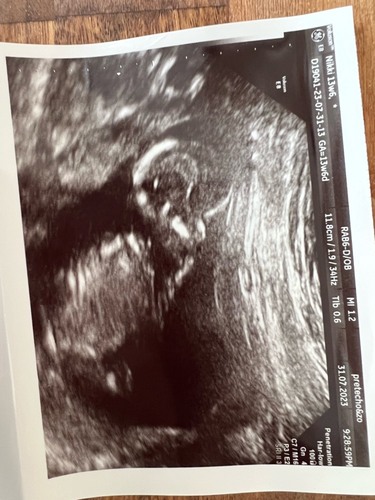

@nubster foto van de echo vandaag! Hopelijk wat duidelijker dan de foto die ik gisteren plaatste. Wat denk je? 🤗

@nubster foto van de echo vandaag! Hopelijk wat duidelijker dan de foto die ...

Ik vermoed 💙 Heb je meer foto's meegekregen?